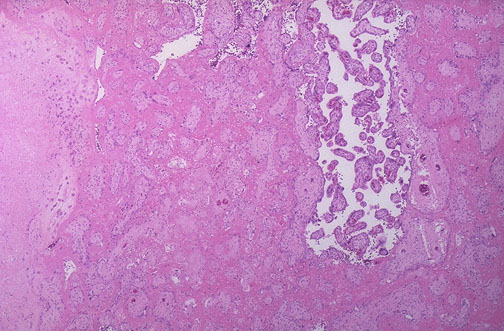

| The decidua is at the left, from which extends into the villi extensive deposits of fibrin, and the villi are becoming infarcted. This is known as maternal floor infarction. This condition can cause uteroplacental insufficiency and fetal demise. It is uncommon, but this condition has a tendency to recur in subsequent pregnancies. |